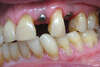

Phase de cicatrisation (intermédiaire) avec pont provisoire collé